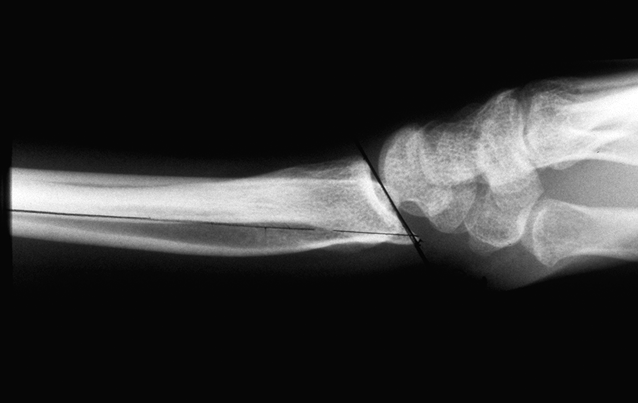

Case 2 - closed reduction